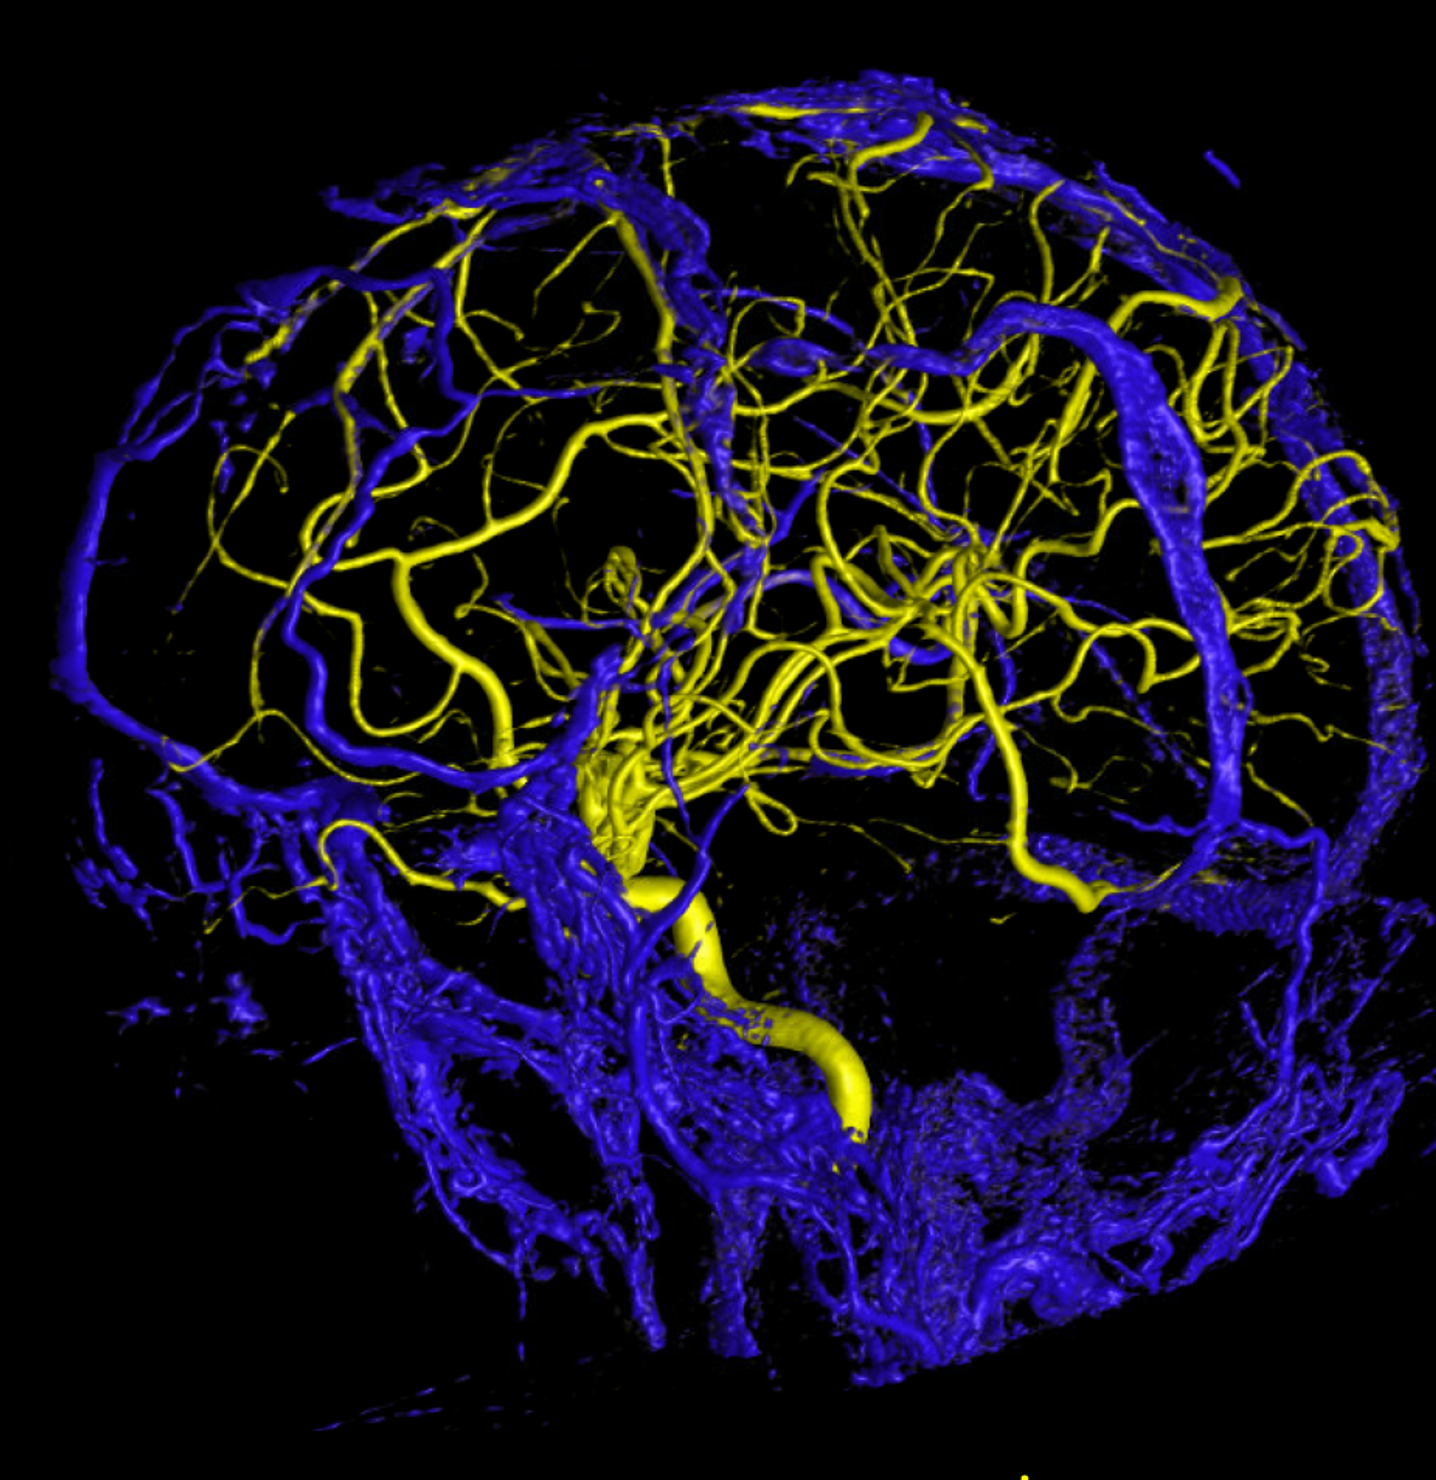

Below are some volumetric images, before we dive in

Pause movies to scroll thru individual frames